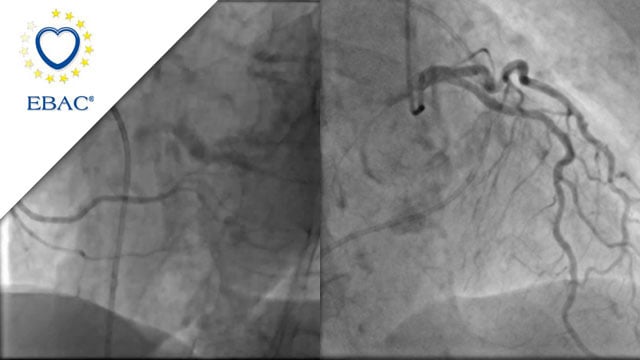

How should I treat a torrential tricuspid valve regurgitation in a young patient who remains symptomatic despite optimal medical therapy?

How should I treat a torrential TR in a young patient who remains symptomatic despite OMT?

A frail patient presents with worsening NYHA class III dyspnoea and peripheral oedema despite optimal medical therapy...